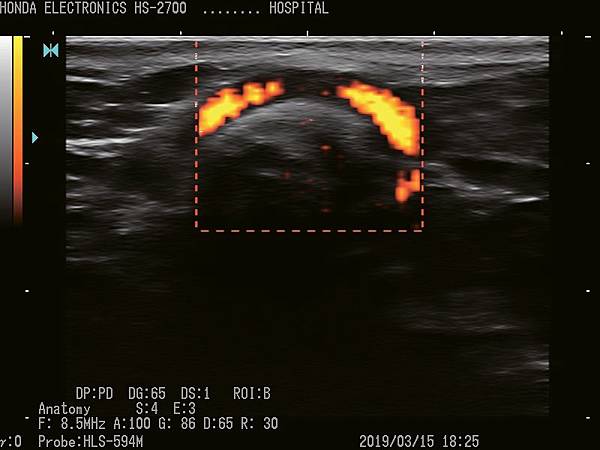

HS-2700支持CFM(彩色血流向)和PD(功率杜普勒)模式。

它們將適應廣泛的醫療應用。